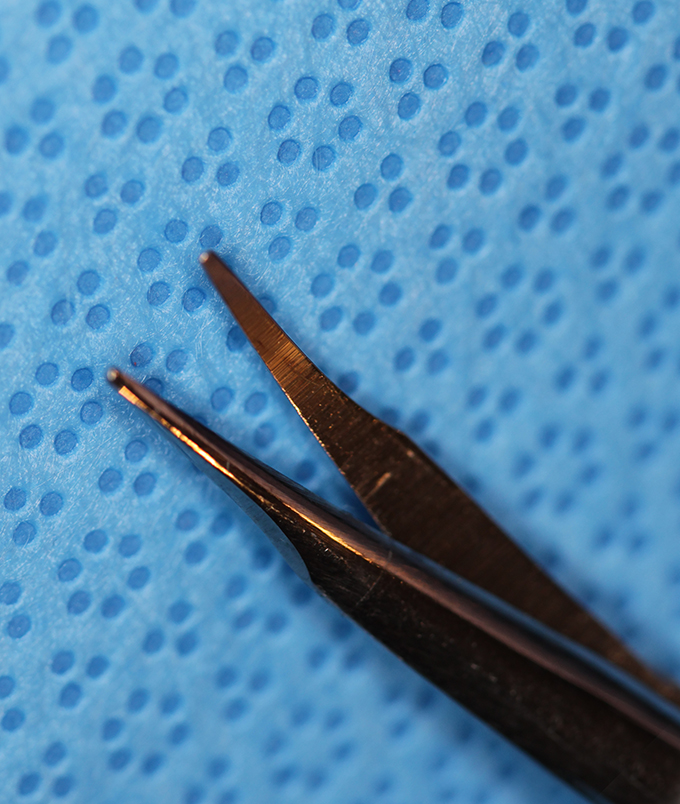

Bonn Forcep .12 Teeth

(aka Bonn Forceps)

catalog number: Storz E1809

Typical Use(s): Holding delicate tissue such as a scleral flap during glaucoma surgery; Has fine teeth smaller than classic .12 forceps

Bonn Forcep .12 Teeth - Enlarged

(aka Bonn Forceps)

catalog number: Storz E1809

Typical Use(s): Holding delicate tissue such as a scleral flap during glaucoma surgery; Has fine teeth smaller than classic .12 forceps